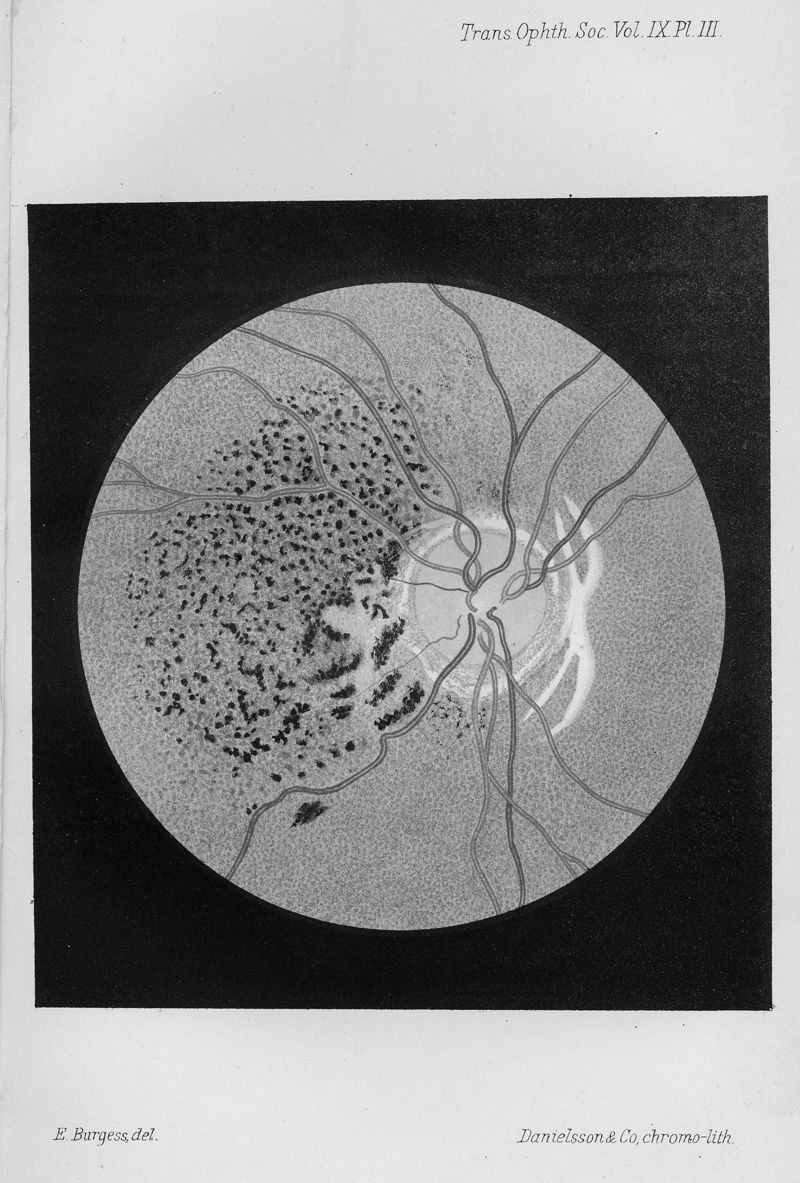

HUTCHINSON, J., Jr.

In : Transactions of the Ophthalmological Societies of the United Kingdom,

1889, Vol. 9, pp. 116-25

HUTCHINSON, J., Jr.

In : Transactions of the Ophthalmological Societies of the United Kingdom,

1889, Vol. 9, pp. 116-25